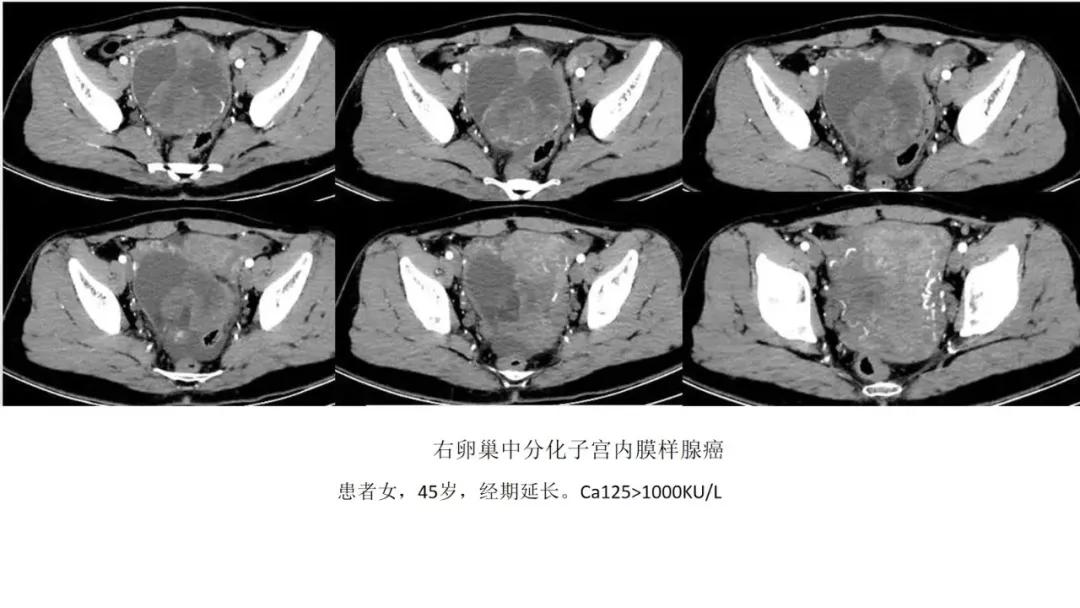

- 子宫内膜样癌与透明细胞肿瘤临床、影像表现比较类似,是微差别的上皮双胞胎

病理:卵巢子宫内膜样癌